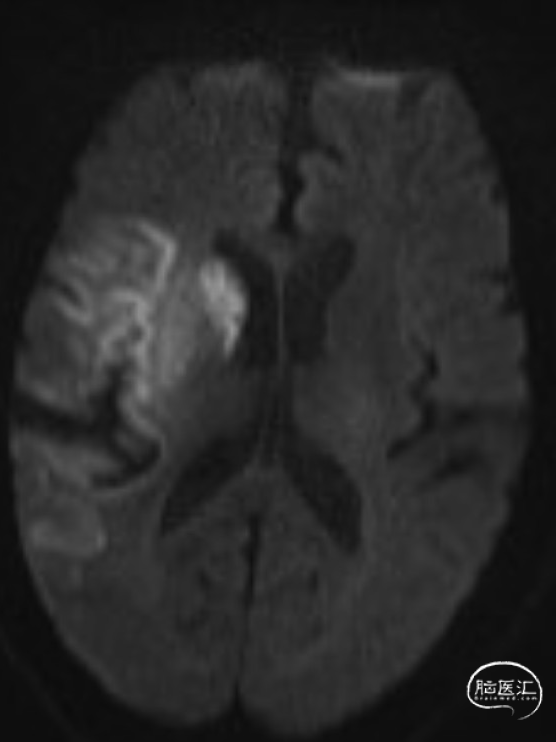

查头颅MRI:右侧基底节区、右侧顶颞岛叶急性脑梗死。